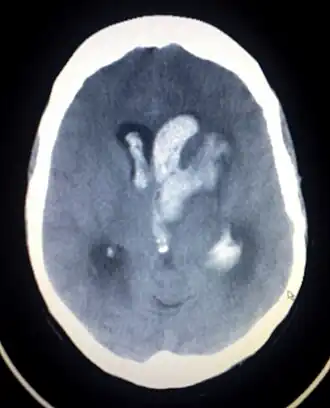

La hemorragia intracraneal ocurre cuando de forma espontánea y súbita hay ruptura de un vaso sanguíneo dentro del cerebro.[1] Ello resulta en sangrado que se acumula en el parénquima cerebral causando una repentina hipertensión intracraneal y un probable accidente cerebrovascular hemorrágico. Las hemorragias intracraneales son emergencias médicas asociadas a una alta morbilidad y mortalidad. La tomografía es la prueba más sensible para el diagnóstico de una hemorragia intracerebral.[2]

Hay dos tipos principales de hemorragias intracraneales no traumáticas, la hemorragia intraparenquimatosa y la hemorragia subaracnoidea.

La hemorragia intraparenquimatosa constituye la primera causa de muerte por hemorragias cerebrales, aproximadamente un 16% de los pacientes fallecen indiferentemente del tratamiento.[cita requerida] La hipertensión arterial es la principal causa predisponente en el 80% de los casos.[3] Otros trastornos asociados son una malformación arteriovenosa (MAV) cerebral, los tumores, y la diátesis hemorrágica.

La vasculopatía hipertensiva afecta el putamen en un 50-60%, el tálamo, protuberancia y los hemisferios cerebelosos. Esta hipertensión prolongada produce esclerosis arteriolar en las arteriolas que penetran estos sitios en el cerebro. Se desarrollan luego pequeñas aneurismas por debilitamiento y dilatación segmentaria que predisponen a la rotura del vaso.

La evolución clínica depende del tamaño y localización de la lesión. En pacientes mayores de 70 años, el 10% de las hemorragias cerebrales se debe a la presencia de amiloide en las arterias cerebrales. La hemorragia que se aprecia en la periferia de los hemisferios cerebrales se llama hemorragia intracerebral lobular, mientras que si aparece en otras estructuras cerebrales como el cerebelo o el tálamo, se llama hemorragia intracerebral profunda.[1]